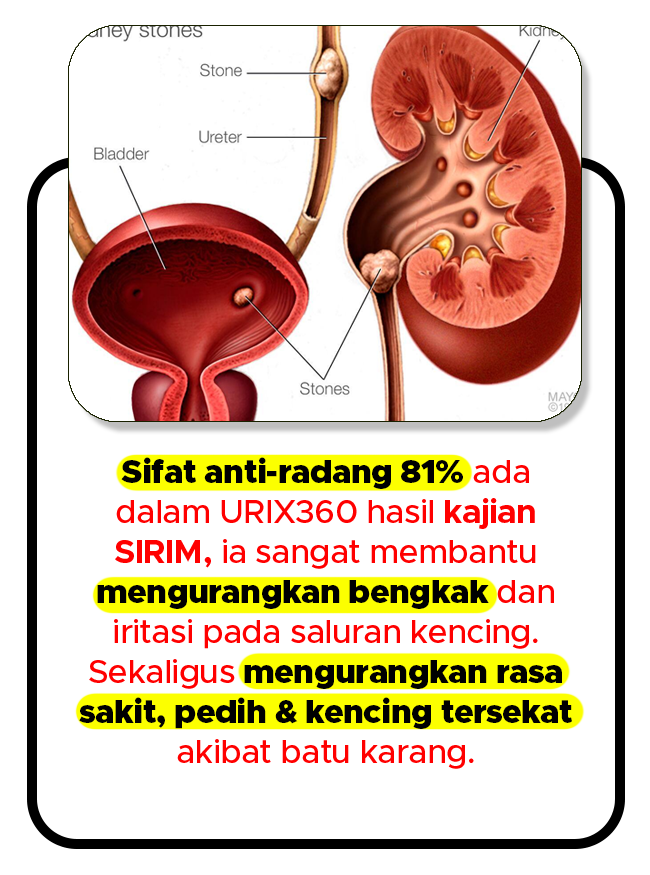

ELAK TEKANAN PUNDI KENCING

Gambar Rajah Fungsi Urix360